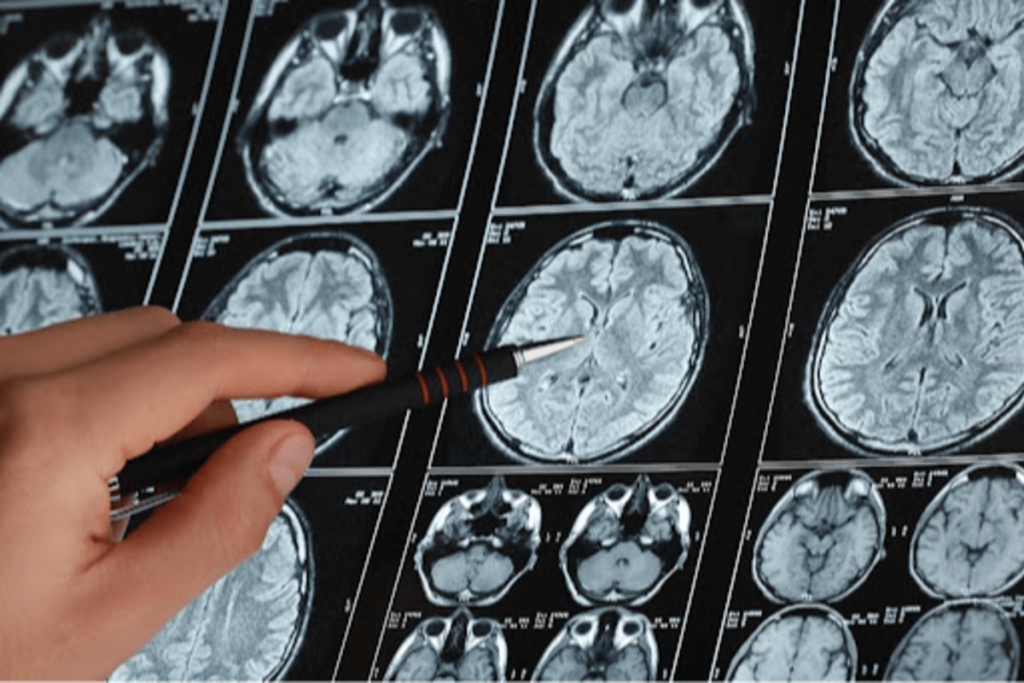

Mediante pruebas en ratones modificados genéticamente y muestras de tejido cerebral humano, el estudio-publicado en ‘Journal of Neuroinflammation’- ha confirmado que esta desregulación de los microRNA produce estados proinflamatorios intestinales.

Dado que también aparece en el intestino de modelos animales, los investigadores consideran viable analizarlo en biopsias intestinales o incluso en fluidos biológicos como plasma o líquido cefalorraquídeo, que rodea al cerebro y la médula espinal, para avanzar hacia un diagnóstico más temprano.